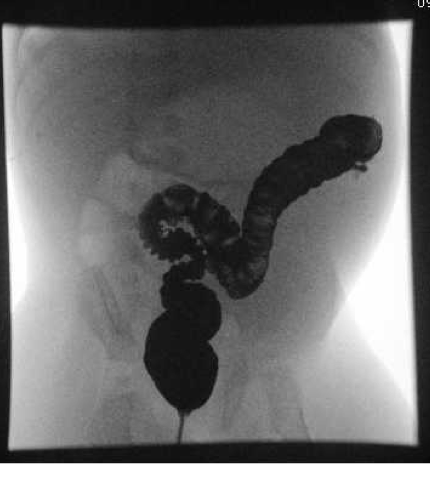

Barium enema